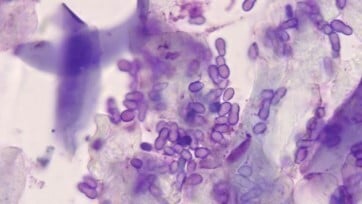

- 5 to 10 minutes: general assessment of skin, to establish if an allergic component is driving the otitis, as well as otoscopic examination of the ears, sampling for in-house cytology and microscopy (Figure 1)

- Repeat until the effluent runs clear; this is especially important for Pseudomonas otitis and sometimes for Malassezia otitis (Figure 1A) which can create a slimy biofilm which protects the microbes, making medication unable to penetrate